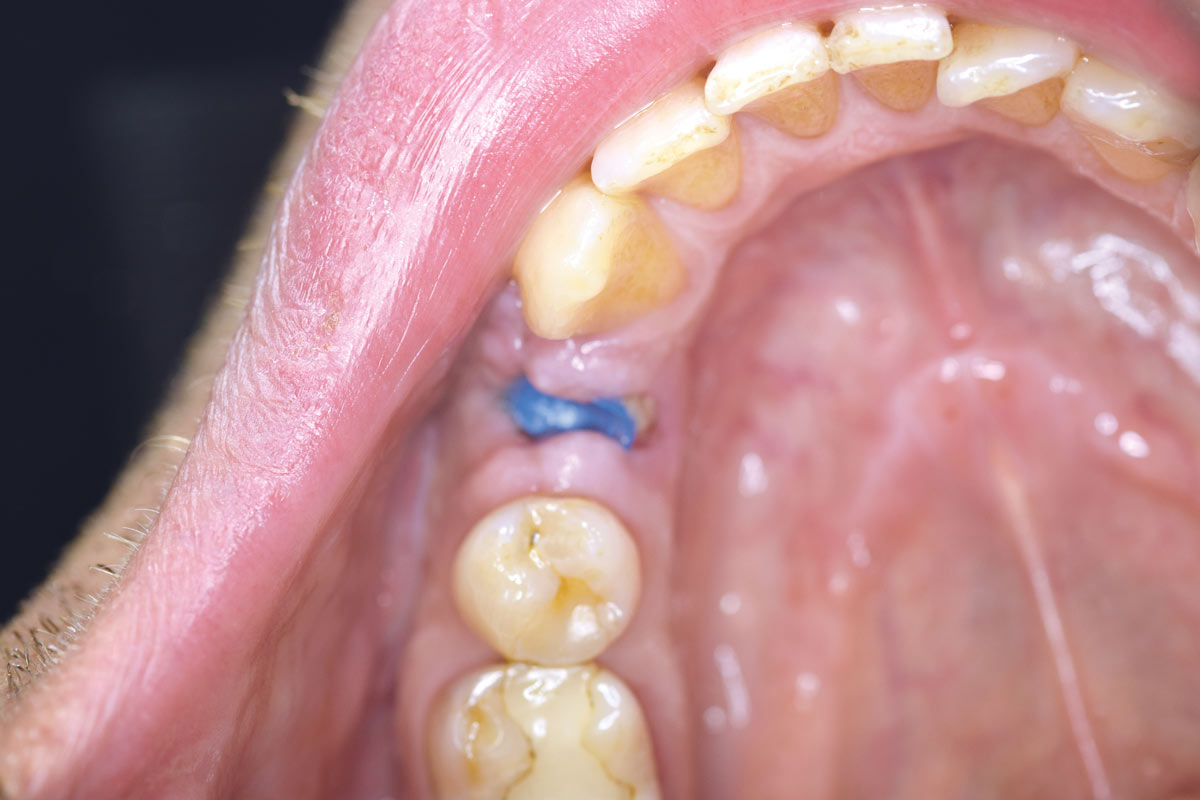

Posterior socket preservation using maxgraft® and permamem® - Dr. C. Landsberg

Tooth 16 furcation involvement with gingival marginal recession and large Class 5 filling